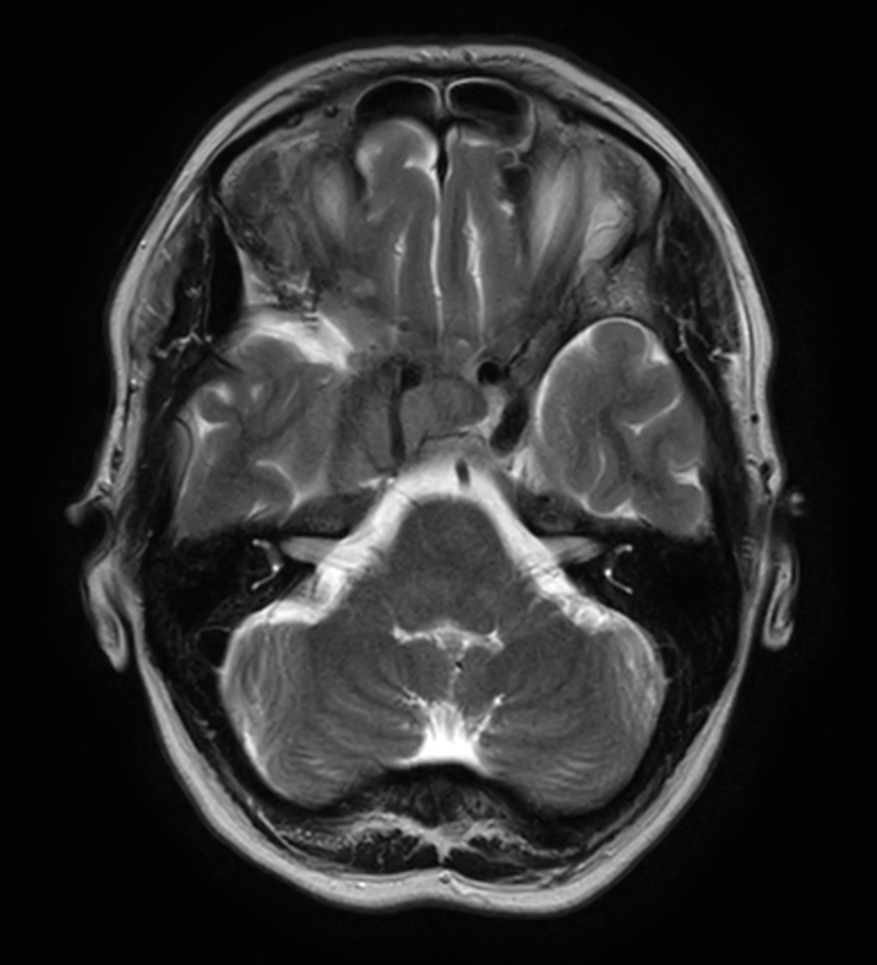

Young female referred for stereotactic treatment underwent MRI simulation.  Flex L Coils in combination with integrated FlexCoverage Posterior coil were used to image the patient in the stereotactic mask in Ingenia MR-RT 1.5T.

Axial 3D T2w TSE FLAIR